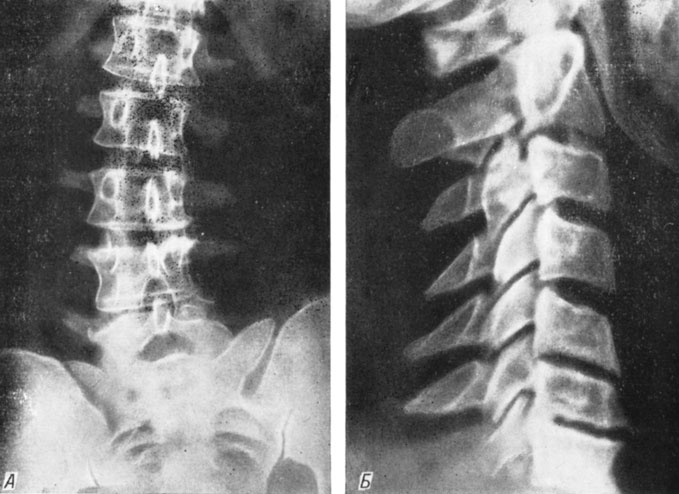

Рентгеновские снимки крестцово-копчикового отдела позвоночника